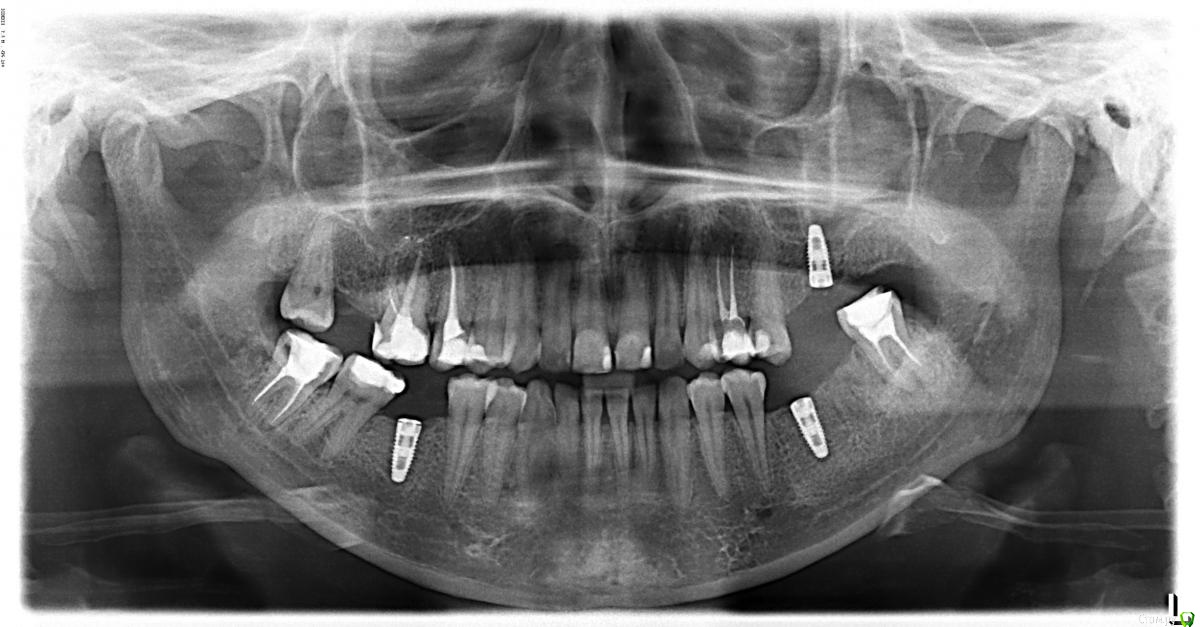

Исследование на рентгене после имплантации зубов

Раздел: Снимки-откровения